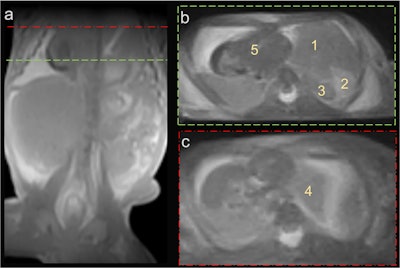

Fetus 2, with a left-sided diaphragmatic hernia (a) characterized by displacement of the liver (1), spleen (2), and intestinal loops (3) into the left hemithorax, along with left lung hypoplasia (4) and a rightward shift of the heart (5).All figures courtesy of Dominic Gascho and Dr. Anna Kuntze and International Journal of Legal Medicine